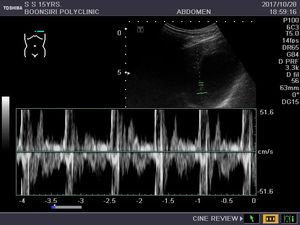

This is me in the picture is a heartbeat stroke. I am 16 years old, I am Thai, the symptoms are fast heartbeat, some time there are tired, tired, please give advice on health care with me.